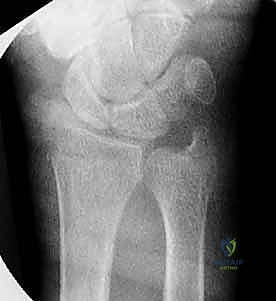

هو المعيار الذهبي الأساسي. يتم أخذ صور من زوايا متعددة (أمامية خلفية، وجانبية) لتحديد:

* موقع الكسر بدقة.

* مدى تفتت العظم.

* مدى انزياح العظم عن مكانه الطبيعي.

* تأثر سطح المفصل (الكسور داخل المفصلية).

3. التصوير المقطعي المحوسب (CT Scan)

في حالات الكسور المعقدة أو المفتتة التي تمتد إلى داخل المفصل، يطلب الدكتور هطيف إجراء أشعة مقطعية. توفر هذه الأشعة صوراً ثلاثية الأبعاد تسمح للجراح بالتخطيط الدقيق للعملية الجراحية، ومعرفة أماكن الشظايا العظمية بدقة مليمترية.